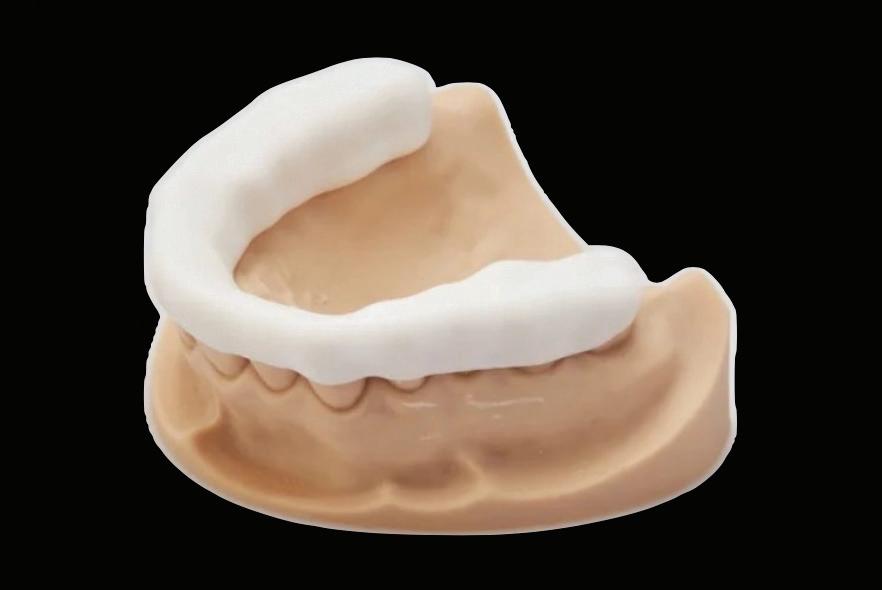

– 5 cavity classes